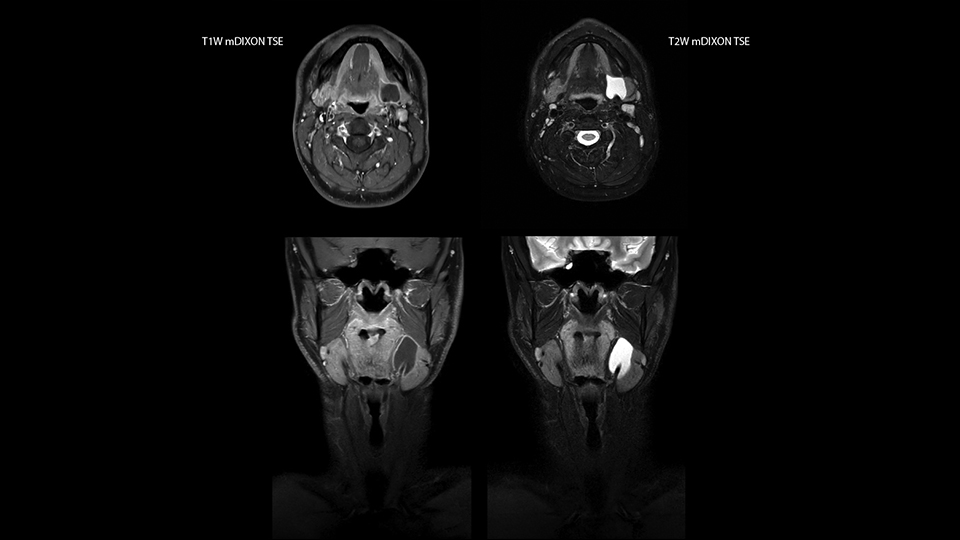

“Our DMG Lisle location includes a cancer center, so soft tissue neck scans, brachial plexus scans, and prostate scans are common. For these exams, mDIXON TSE provides excellent images with and without fat suppression all while helping us reduce repeats and work more efficiently,” Mr. Duffy says.

“With the 2-echo Philips mDIXON TSE the timing is short and the fatsat is very robust. The biggest thing is that you know your fat suppression will be good, even in thin patients or large patients that are off-center,” Mr. Sybesma says.

“Since we work in fixed time slots, not having to repeat scans is key for us,” Mr. Duffy adds. “With mDIXON TSE we get high quality results the first time – unless of course the patient absolutely jumps off the table. For us, that’s significant, because just a single repeat scan could put us behind schedule.

“mDIXON TSE raises our diagnostic confidence with its homogeneous

fat suppression. Neck exams and rheumatology patients are two examples where mDIXON TSE is especially useful,” Dr. Kaakaji says. “For us it’s also an efficiency boost in exams where we need pre and post T1-weighted images with great fat suppression.”